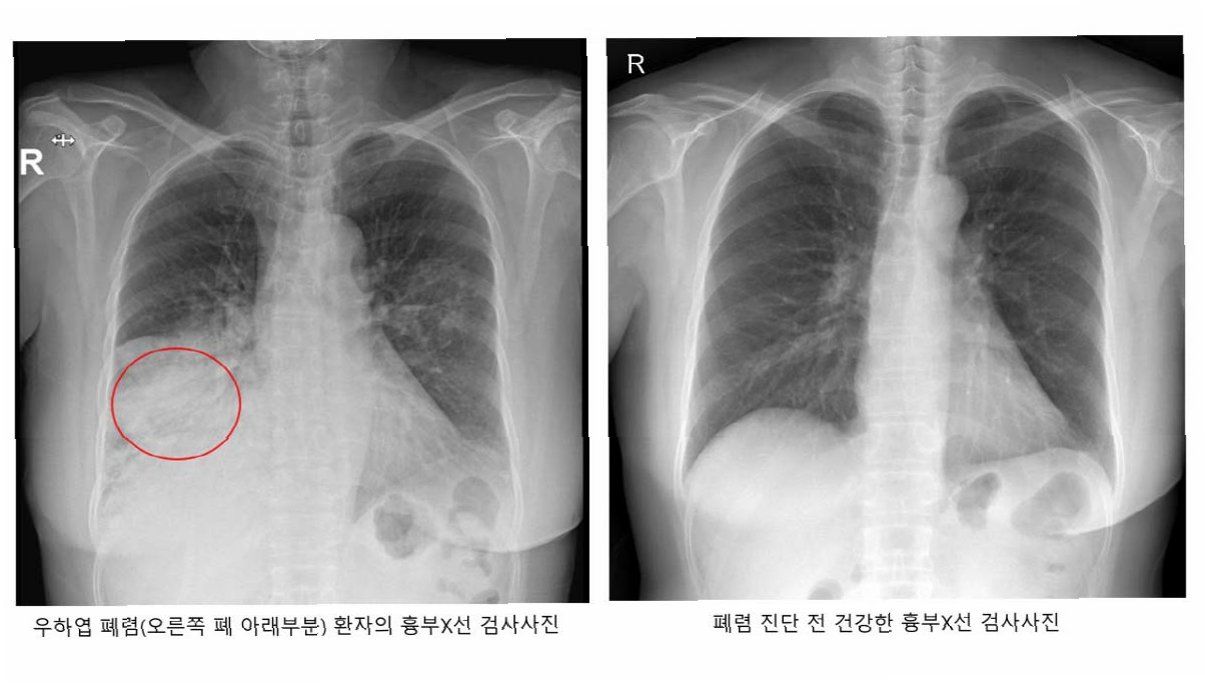

폐렴 증상이 의심될 경우, 즉시 병원을 방문하여 정확한 진단과 적절한 치료를 받아야 합니다. 특히 고령층은 증상이 모호하여 자가 진단으로 치료 시기를 놓치는 경우가 많으므로 주의해야 합니다. 병원에서는 흉부 X-ray, 혈액 검사 등을 통해 폐렴을 진단하고, 원인균에 맞는 항생제, 항바이러스제 등을 처방합니다. 필요에 따라 산소 치료, 수액 치료 등을 시행하기도 합니다. 폐렴은 조기에 발견하여 치료할수록 예후가 좋으므로, 의심 증상이 나타나면 망설이지 말고 의료기관을 방문하십시오.